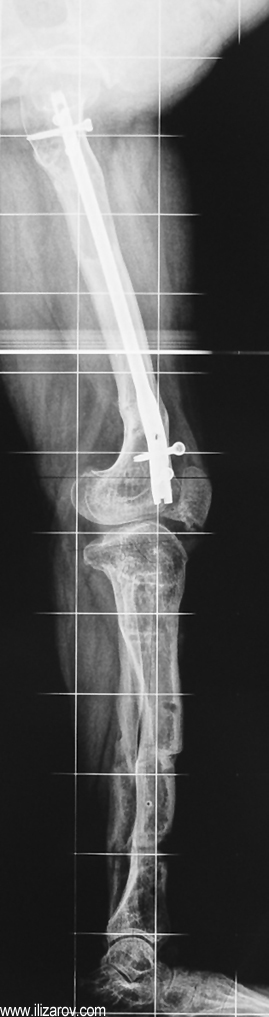

Hipofosfatemik raşitizmin neden olduğu bozukluk büyüme plağına çok yakın olduğu için büyük bir deformite ve ciddi dizilim bozukluğu ortaya çıkar. Bu nedenle cerrahi öncesi değerlendirmede sıklıkla birden çok deformite merkezi (CORA) bulunur ve deformitenin düzeltilmesi için birden çok seviyeden osteotomi yapılması gerekir. Deformitenin düzeltilmesi için en sık kullanılan yöntemler Ilizarov yöntemi ya da monolateral eksternal fiksatör kullanılarak akut ya da tedrici deformite düzeltilmesidir. Kliniğimizde uygulanan fiksatör yardımlı çivileme yönteminde deformite eksternal fiksatör kullanılarak akut olarak düzeltildikten sonra intramedüller çivi ile stabilizasyon sağlanmakta, uzatma yapılmayacaksa eksternal fiksatör cerrahi sona ermeden çıkartılmakta, uzatma yapılacaksa (çivi üzerinden uzatma) uzatma tamamlandıktan sonra fiksatör çıkartılmaktadır. Bu sayede tel dibi enfeksiyonu riski ortadan kalkmakta, hipofosfatemik raşitizm tedavisinde önemli sorunlar olan koreksiyon kaybı ve deformite nüksü önlenmekte, hastaya erken hareket verilerek tam yükle yürümesine izin verilmekte ve eksternal fiksatör süresi azaldığı için hasta konforu artmaktadır.

Vaka 1